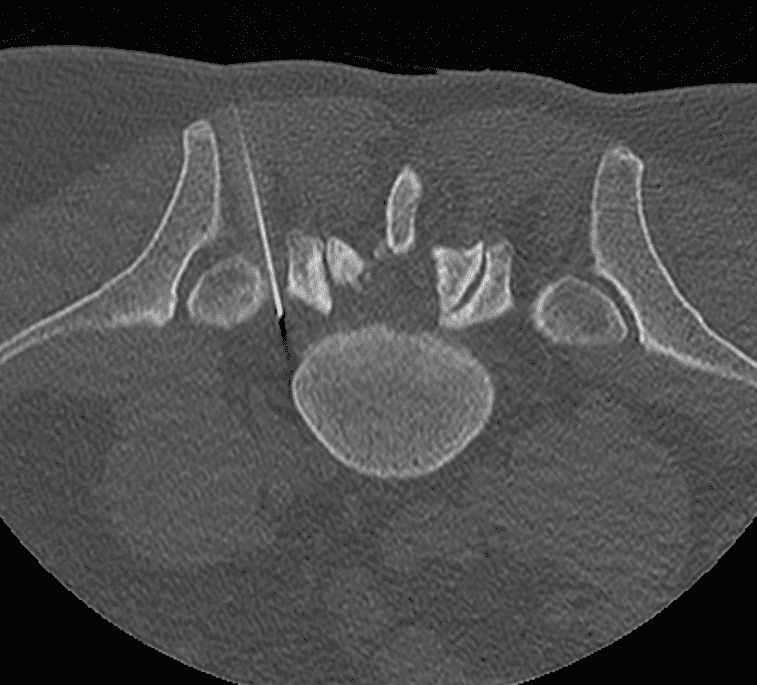

Scanner

Une imagerie (scanner ou IRM) est réalisée en amont pour établir le diagnostic, évaluer l’anatomie discale et planifier la trajectoire d’insertion.

Le guidage en temps réel par fluoroscopie ou scanner assure une précision optimale, minimisant ainsi le risque de lésion des structures adjacentes.

Contrôle final

Un contrôle imagerie est effectué en fin d’intervention pour vérifier la qualité de la décompression et la bonne répartition des espaces discaux, garantissant ainsi l’efficacité du geste.